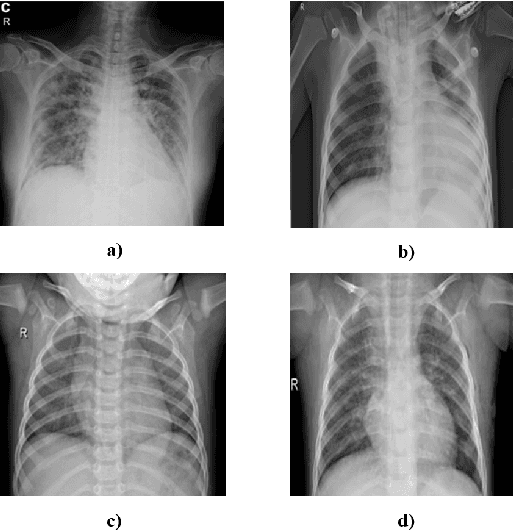

Abstract:The new coronavirus 2019, also known as COVID19, is a very serious epidemic that has killed thousands or even millions of people since December 2019. It was defined as a pandemic by the world health organization in March 2020. It is stated that this virus is usually transmitted by droplets caused by sneezing or coughing, or by touching infected surfaces. The presence of the virus is detected by real-time reverse transcriptase polymerase chain reaction (rRT-PCR) tests with the help of a swab taken from the nose or throat. In addition, X-ray and CT imaging methods are also used to support this method. Since it is known that the accuracy sensitivity in rRT-PCR test is low, auxiliary diagnostic methods have a very important place. Computer-aided diagnosis and detection systems are developed especially with the help of X-ray and CT images. Studies on the detection of COVID19 in the literature are increasing day by day. In this study, the effect of different batch size (BH=3, 10, 20, 30, 40, and 50) parameter values on their performance in detecting COVID19 and other classes was investigated using data belonging to 4 different (Viral Pneumonia, COVID19, Normal, Bacterial Pneumonia) classes. The study was carried out using a pre-trained ResNet50 convolutional neural network. According to the obtained results, they performed closely on the training and test data. However, it was observed that the steady state in the test data was delayed as the batch size value increased. The highest COVID19 detection was 95.17% for BH = 3, while the overall accuracy value was 97.97% with BH = 20. According to the findings, it can be said that the batch size value does not affect the overall performance significantly, but the increase in the batch size value delays obtaining stable results.